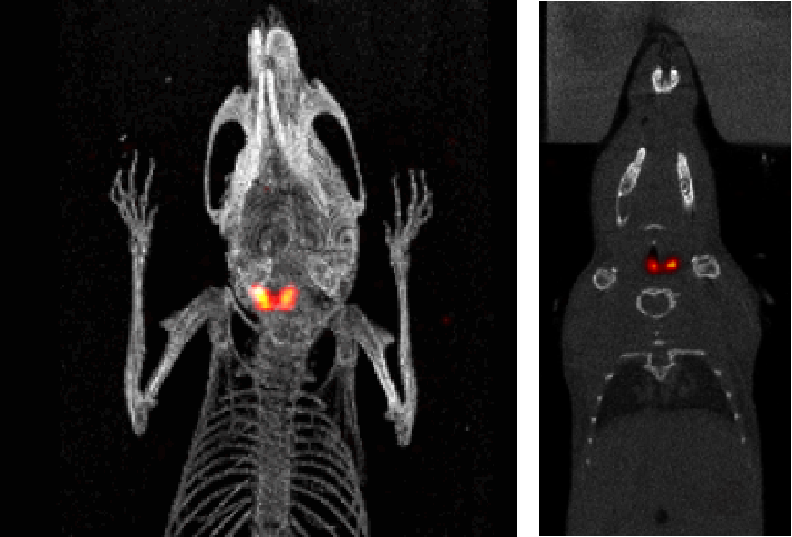

5、甲狀腺SPECT成像

I123小鼠甲狀腺SPECT成像:檢測(cè)小鼠的甲狀腺,9.4MBq(250μCi)I123,采集時(shí)間:30min。

甲狀腺成像.png